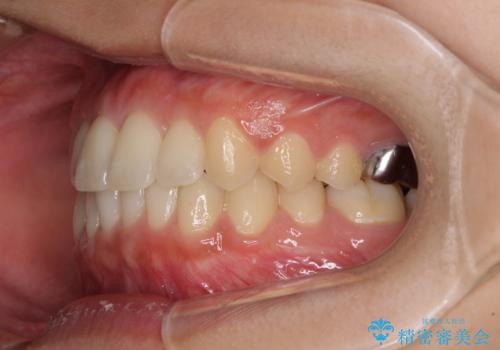

海外勤務中のインビザラインによる矯正治療

- 前歯のクロスバイトを気にして来院され患者様です。

定期的に日本には帰国するものの、日ごろは海外でお仕事をされているとのことで、インビザラインによる治療を希望されました。

トラブルが起こった時に対応ができない、来院を帰国のタイミングに合わせなければならないため治療が長期化するなど困難はありますが、ワイヤー矯正と比べると治療を進めやすいといったメリットがあるので、インビザラインにて矯正治療を行うこととしました。

治療期間が世界的な感染症の流行時期と重なったため、海外と日本での往来が困難となり、治療継続が懸念されました。

それでも、しっかりとマウスピースを装着してくださったので、大きなトラブルもなく治療を終えることができました。